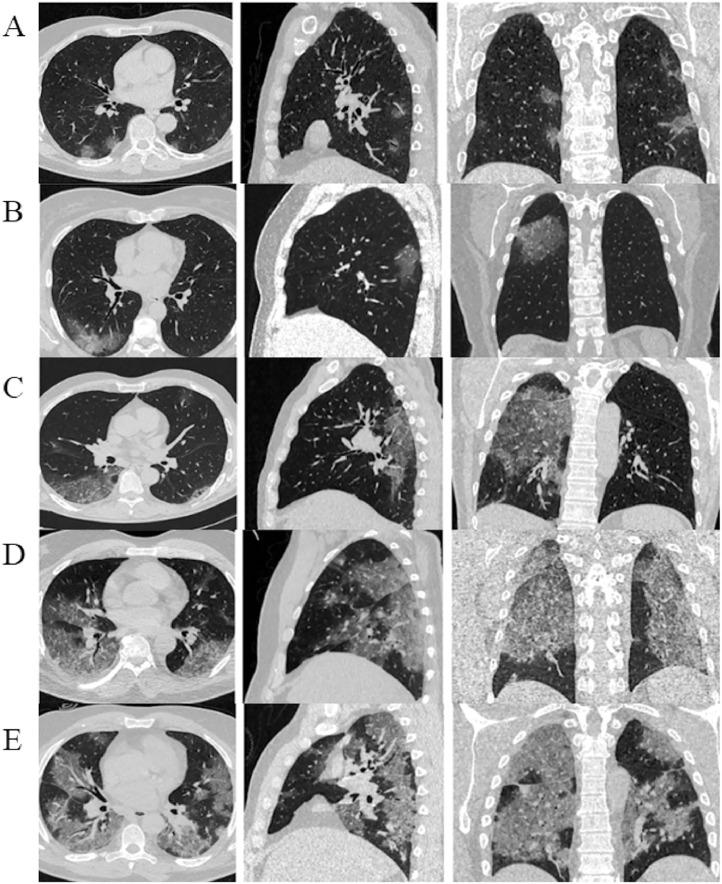

Patients with mild and moderate COVID-19 had up to 45% lung injuries, whereas critical patients had 55%. However, patients with mild and moderate COVID-19 typically had low-level lung injuries. Ground-glass (68.1%), consolidation (48.8%), opacity (36.3%), and nodular (6.9%) lung lesions were the most prevalent in patients with COVID-19. Patients with COVID-19 infected with the Delta variant had worse lung injury than those infected with the Alpha and Omicron. People vaccinated with ≥2 doses showed a lower risk of lung injury than those vaccinated with <1 dose. Patients <18 years old were less likely to have a lung injury than patients >18 years old. The treatment outcomes were unaffected by the severity of the lung injury.

轻度和中度COVID-19患者的肺损伤发生率高达45%,而重症患者为55%。然而,轻度和中度COVID-19患者通常为低水平肺损伤。磨玻璃影(68.1%)、实变(48.8%)、opacity(36.3%)和结节(6.9%)是COVID-19患者中最常见的肺部病变。感染德尔塔变异株的COVID-19患者比感染阿尔法和奥密克戎变异株的患者肺损伤更严重。接种≥2剂疫苗的人比接种<1剂疫苗的人发生肺损伤的风险更低。<18岁的患者比>18岁的患者发生肺损伤的可能性更小。治疗结果不受肺损伤严重程度的影响。